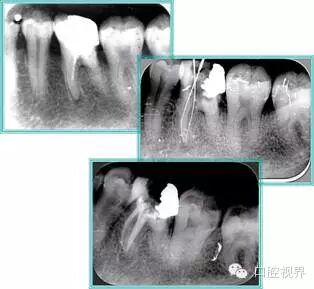

6. 术后 X 线片

术后 X 线片用来评定根管充填 长度、致密度(管壁清晰、侧枝)等指标。

口腔H锉怎么消毒根管治疗的细节把握(细节决定成败)_https://www.jmylbn.com_新闻资讯_第16张

左图为根管充填术后 X 线片。图中可见,根管充填较好。右下图有白色小点,为侧方加压导致糊剂挤出所致,表明根管充填比较致密。

致密、恰到好处的充填可去除干净根管里感染灶,机体逐渐恢复。

口腔H锉怎么消毒根管治疗的细节把握(细节决定成败)_https://www.jmylbn.com_新闻资讯_第17张

多根牙时候需进行偏移投照,正位投照无法说明具体哪根牙根管充填效果。